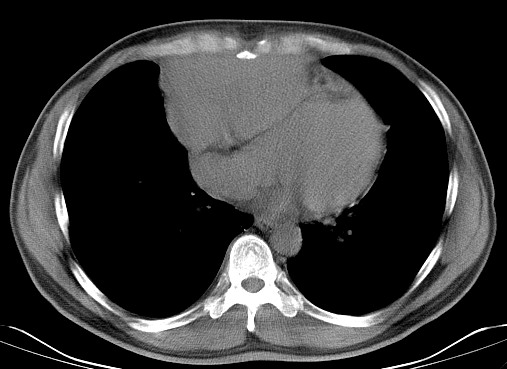

男   40   反复腹痛入院行彩超检查示胸骨右缘4、5肋间不均质回声团

淋巴瘤:前纵隔可见多组肿大的淋巴结,部分融合,有液化坏死

上区却那么有点象占位,胸腺瘤不太象,一点强化也没有,淋巴瘤气管前上腔静后却很干净,下区也点象纵隔积血征,